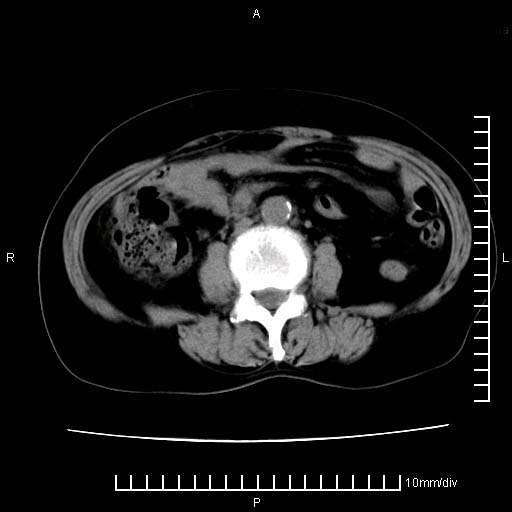

下腹疼痛2月,加重并呕吐2天,下腹压痛,反跳痛。白细胞1万2.

下腹至盆腔较大包块,与邻近肠管关系密切,下腹疼痛2月,加重并呕吐2天,下腹压痛,反跳痛。白细胞1万2.

支持楼上意见:考虑回盲部慢性炎症,并包裹积脓肿。

盆腔脓肿伴盆腔积液

盆腔脓肿伴积液可能性大。